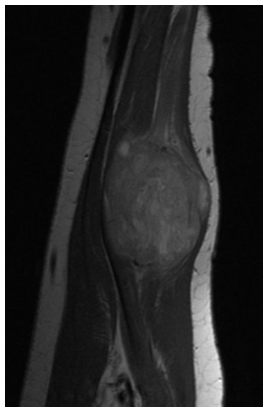

An example of an Leiomyosarcoma MRI is shown.